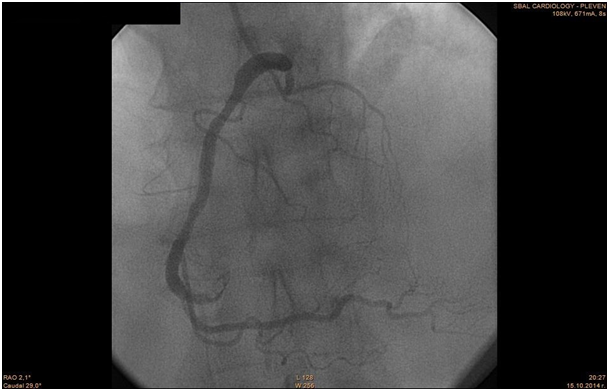

The patient was transferred to the Catheterization Laboratory in order to undergo coronary angiography. The coronary angiography revealed normal anatomy of Left Main Coronary Artery, LAD- 80% mid segment stenosis. LCx - irregularities. RCA - anomalous origin from the left Valsalva sinus. 50% mid segment stenosis, distal occlusion with thrombus. PCI was performed with guiding catheter XB 3.5 6F, coronary guide wire Terumo Runthrough 0.014". Predilation with balloon 2, 75/20 mm and implantation of two drug eluting stents 2, 75/28 mm with overlapping. Post-dilation at the site of overlapping with the balloon of the second stent.

The patient was previously hospitalized for chronic heart failure NYHA class III and ventricular fibrillation, which was treated with a synchronized shock. She also has arterial hypertension present for the past 20 years, permanent atrial fibrillation and type 2 diabetes. For these conditions she was on the following medication therapy: Bisoprolol Fumarate, Telmisartan, Amiodarone, Gliclazide, Metformin, Acenocoumarol, Tavipec and Azithromycin (Figure 46). The cause of the present ischemia is not a result of a mechanical compression of the artery, but is a result of atherosclerosis and plaque rupture with subsequent development of myocardial infarction (Figure 7 & 8).

Figure 6 Final Angiographic result.

Although coronary anomalies are not common in the clinical practice, they should not be underestimated especially in young athletes and physically active people. It is imperative that angina pectoris symptoms in these groups of patients be recognised and diagnosed. Methods used for diagnosis are - history of the present illness, physical examination, ECG, coronary CTA and coronary arteriography. Some coronary anomalies could be asymptomatic during childhood. Their diagnosis in adulthood is due to the clinical manifestation of myocardial ishemia as a result of coronary artery disease and its complications, or by mechanical compression of the anomalous artery. In this case study the patient presents itself with chest pain,acute myocardial infarction and a medical history of ventricular tachycardia. 30 days after the initial hospitalisation, the patient was admited for hospital treatment again,because of the persistent symptomatic significant stenosis of LAD. Coronary angiography revealed optimal result after the PCI of the RCA. There are also no sighs that RCA is situated between the aorta and the pulmonary artery.This proves that the etiology of STEMI in this case was purely due to athrerosclerosis.